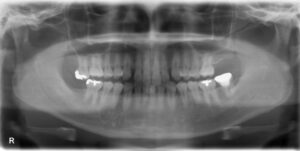

上下顎臼歯3本欠損症例

BEFORE AFTER 65歳女性/上下顎3本欠損/インプラント埋込手術 【治療内容】 右下第二小臼歯、第一大臼歯は義…